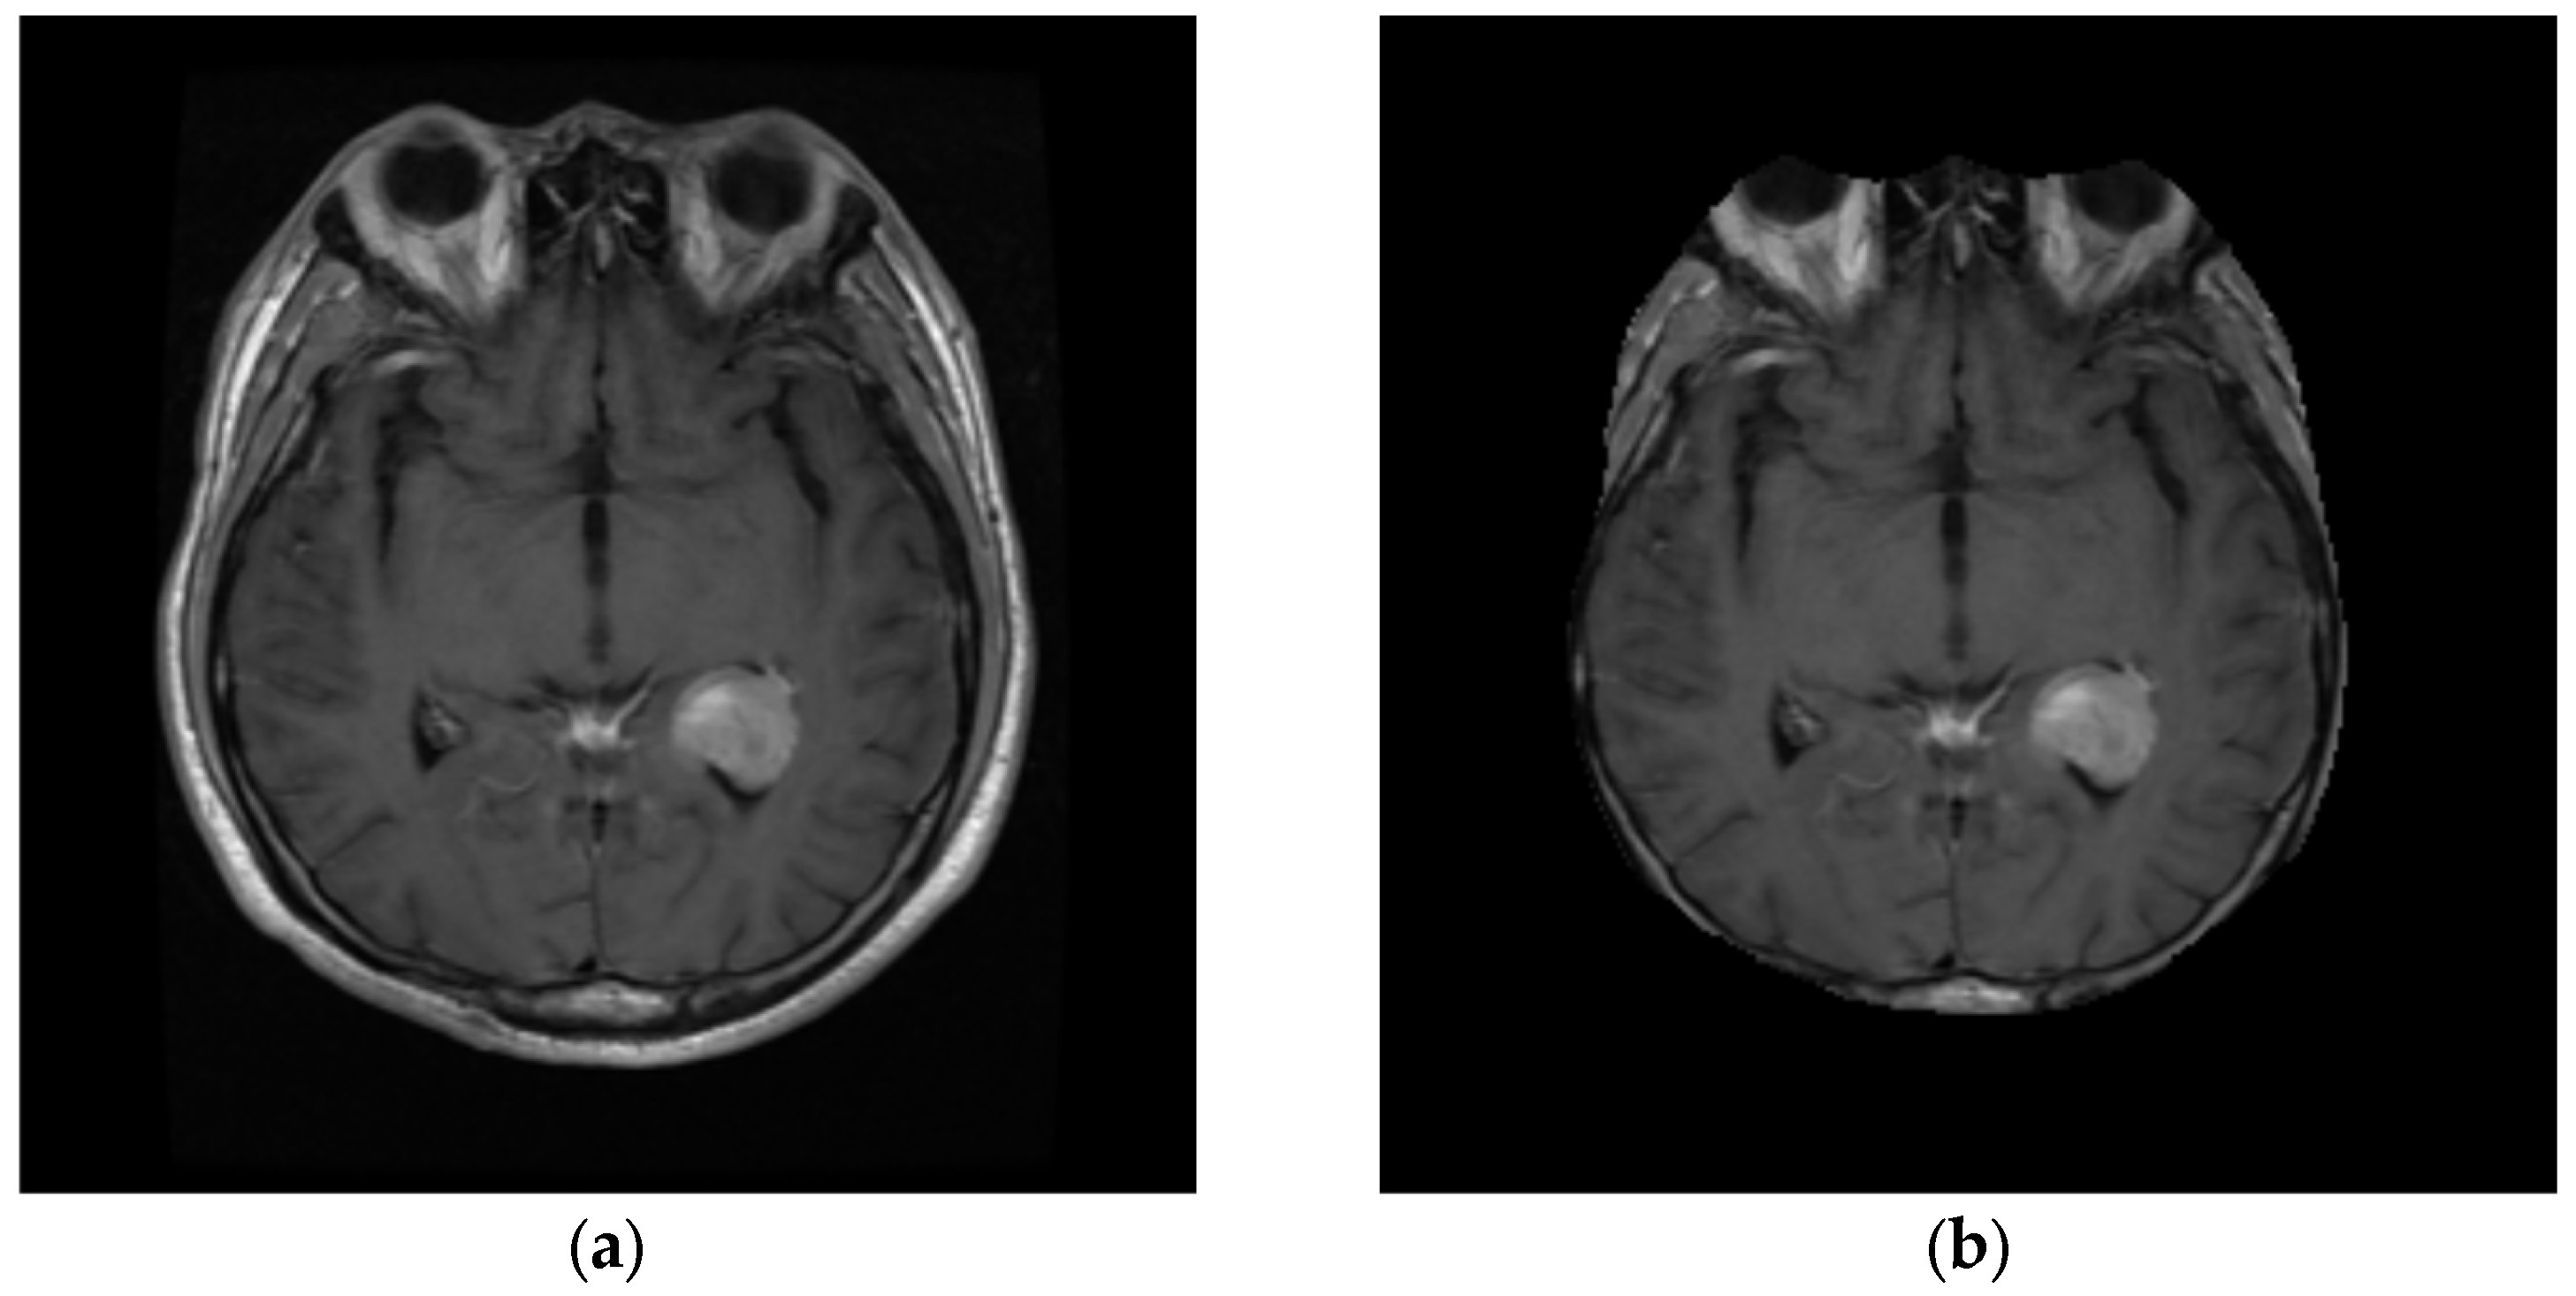

3.1. Image Pre-Processing

4.1.1. Database Description